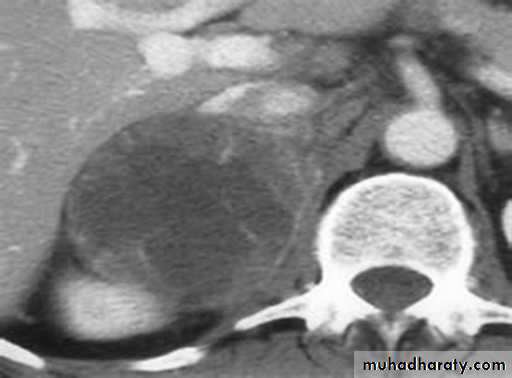

Primary hyperaldosteronism (Conn’s syndrome):

Primary hyperaldosteronism (PHA) is defined by hypertension, hypokalaemia and hypersecretion of aldosterone.

It represent 2% of hypertensive patients.

Its due to:

1- unilateral adrenocortical adenoma 60-80%

2- bilateral micronodular hyperplasia in 20–40%.

MRI or CT should be performed to distinguish unilateral from bilateral disease. Conn’s adenomas usually measure between 1 and 2 cm and are detected by CT with a sensitivity of 80–90%